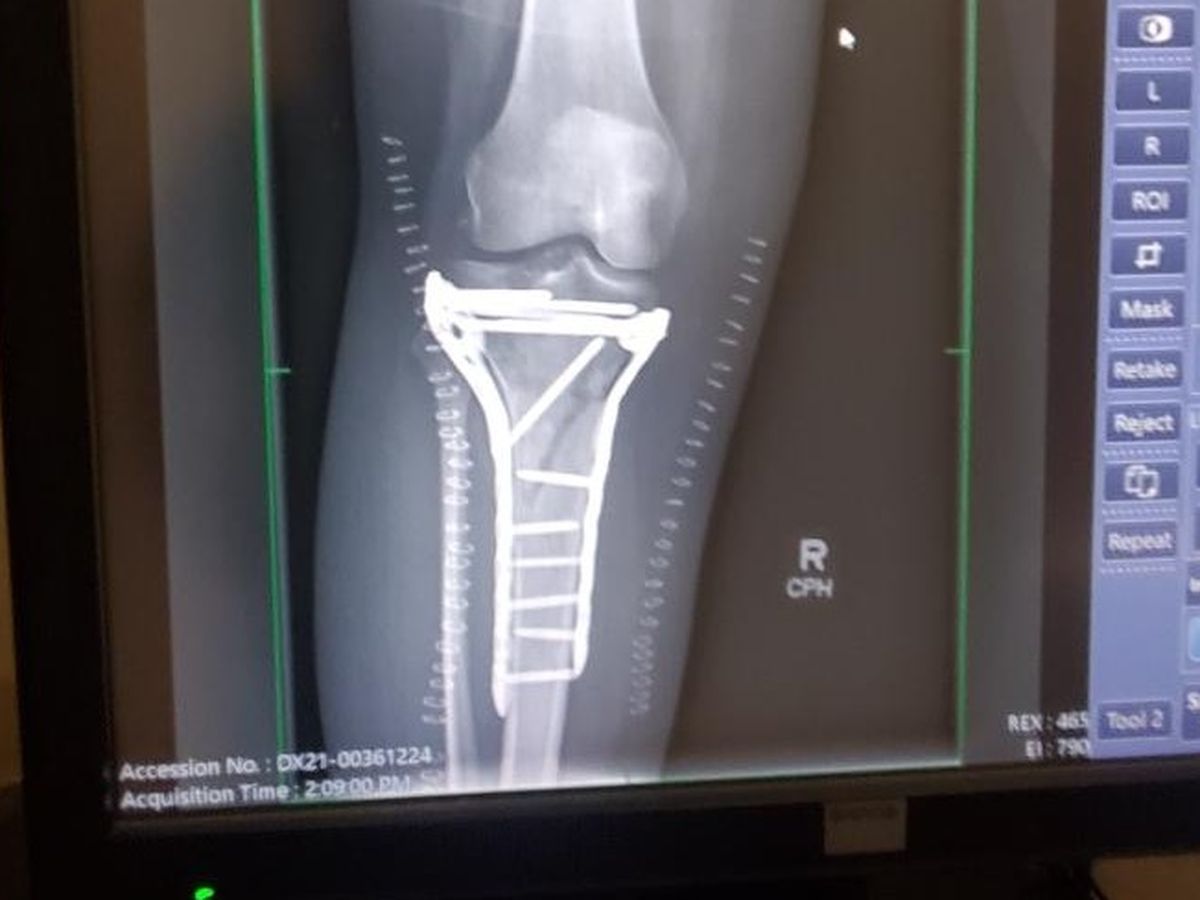

Surgery was needed to reset the bones and straighten my leg. I was put into an external fixation where they screwed this device into my bones to help me keep the bones in place while the swelling went down in my leg. This device was only supposed to be on for two weeks. At the follow-up to schedule the second surgery, the swelling had not gone down enough to put the plates and screws that would replace the external fixation. I was lucky that the fracture was not an open one and I was lucky to keep my leg because of how close the break was to my knee and how serious the fracture was to both bones.

I was in the external fixation for 3 weeks. Then I underwent the second surgery for the plates and screws. The surgery was supposed to be only 4 hours and it took almost 8 hours. According to the CT scan before the first surgery, the tibia bone had five fragments, however they found more during the surgery. I still could not put weight on my leg after the surgery. I was cleared for weight bearing at the beginning of November and had to learn how to walk again. I also had to retrain my brain to recognize my right leg again. I met my goal of walking with a cane before Christmas. I still have a limp and a long way to go before I am “100%” normal. The doctors think that I might not be 100%, but pretty close to it.